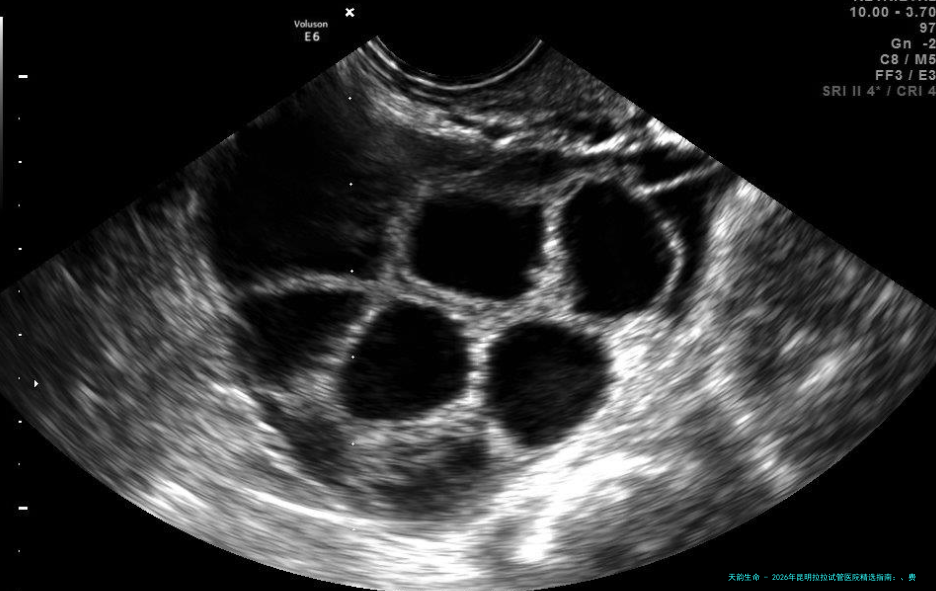

Q:具体的流程是怎样的? A:大致分为五步:1. 前期咨询与体检:选医院,两方完成所有约束检查。2. 证件与文献准备:根据医院要求预备身份证、关系证实、知晓情况同意书等。3. 进入治疗疗程:定方案、促排卵、监测卵泡。4. 取卵与胚胎移植:女方采卵,与供精精子结合成胚胎,培养后移移植子宫。5. 移植后管理:黄体支持,约14天后验孕。